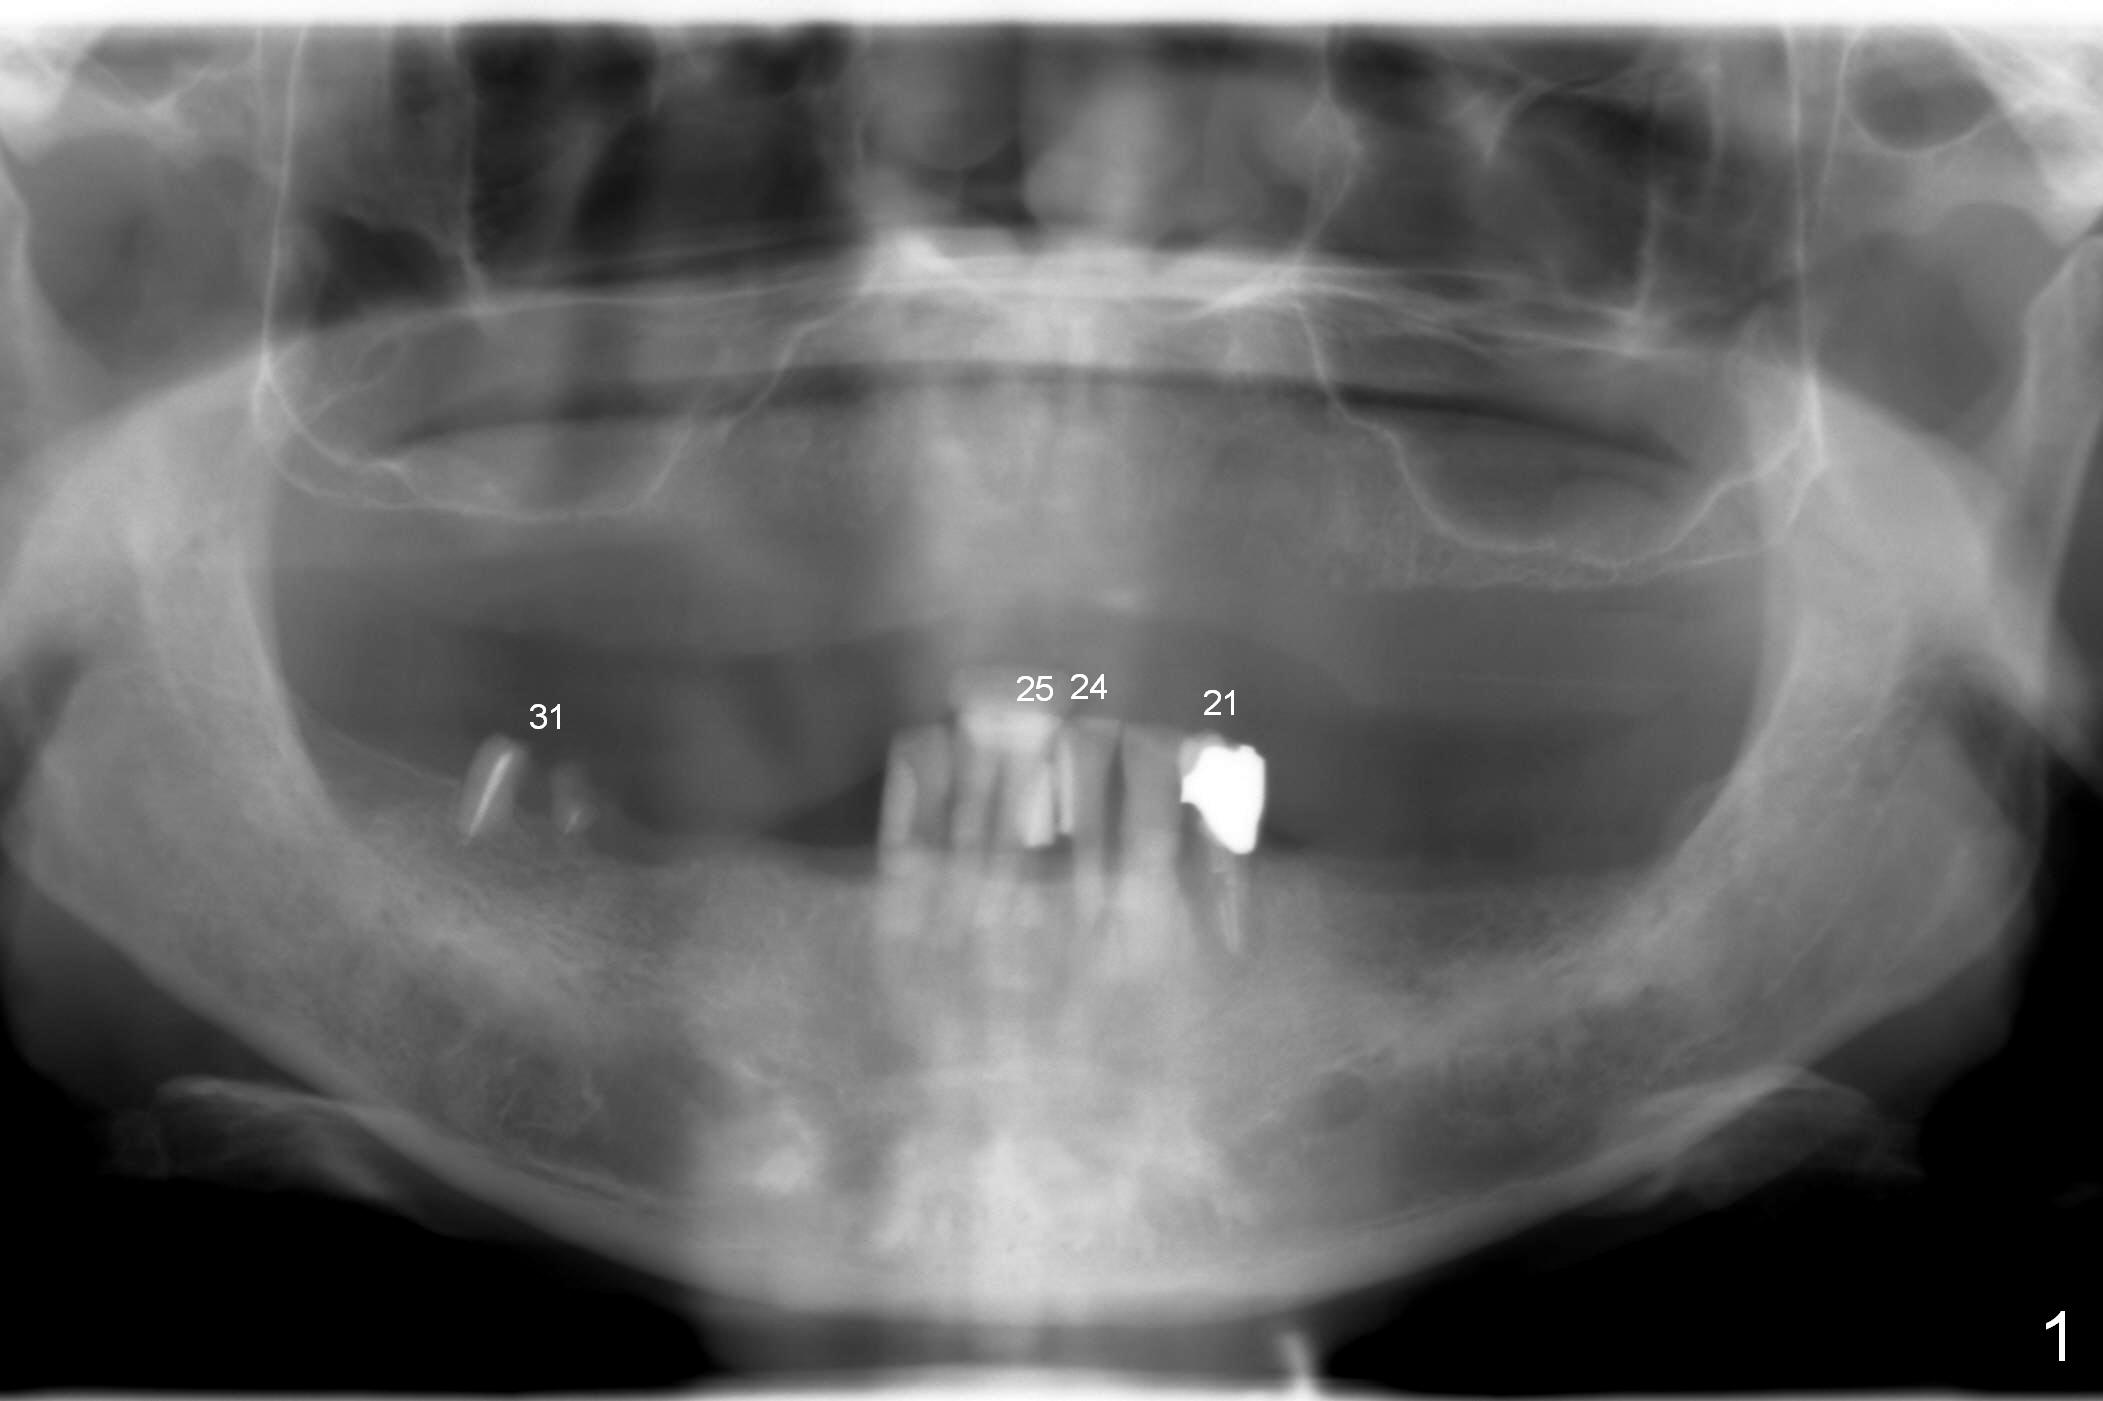

A 72-year-old man presents to clinic for implants because of pain associated with wearing the lower partial. The teeth #21, 24, 25 and 31 seem to be non-salvageable and are going to be replaced by implants so that the lower RPD can be reused (Fig.1). The edentulous ridge is atrophic (Fig.9 *). The upper complete denture appears to be functional. Since the tooth #21 is symptomatic (Fig.2) and the patient has chronic TMJ dislocation, the affected tooth is extracted first (Without antibiotic socket treatment) for immediate implant (Fig.3 (1.5 mm drill (placed more lingually)). The lower RPD is used as a surgical guide (Fig.4 (3 mm drill in place)). When a 3.8x16 mm implant is placed with bone graft (Fig.5 *), the underlying neurovascular bundle is undetected. A small field of panoramic X-ray is retaken; it seems that there is enough clearance from the Mental Foramen (Fig.2,6,7 (red dashed line)) and the Incisive Canal (pink dashed line). The implant is then placed 2 mm more apically (Fig.7) to reduce the chance of periimplantitis since the buccal plate is lost. A 5.5x5(5) mm abutment is placed (Fig.5) with more graft. The access of the abutment is left open so that a part of periodontal dressing is inserted for additional retention (Fig.8,9). The RPD is placed back for adaptation of the dressing. The patient is advised not to wear the RPD postop to reduce micromovement.

The patient returns 2 days postop because of hemorrhage (Fig.10,11 * after removal of loose periodontal dressing). Periodontal dressing is repacked (Fig.12). The hemorrhage may be due to incomplete removal of granulation tissue or invasion of the Incisive vessel intraoperatively, although there is no pain or paresthesia postop. Soft food is recommended without the upper complete denture. A provisional is fabricated (Fig.14 P) nearly 3 months postop (after changing the 5.5x5(5) mm abutment to 4.5x5(4) mm, Fig.13) when an implant is being place is #31.